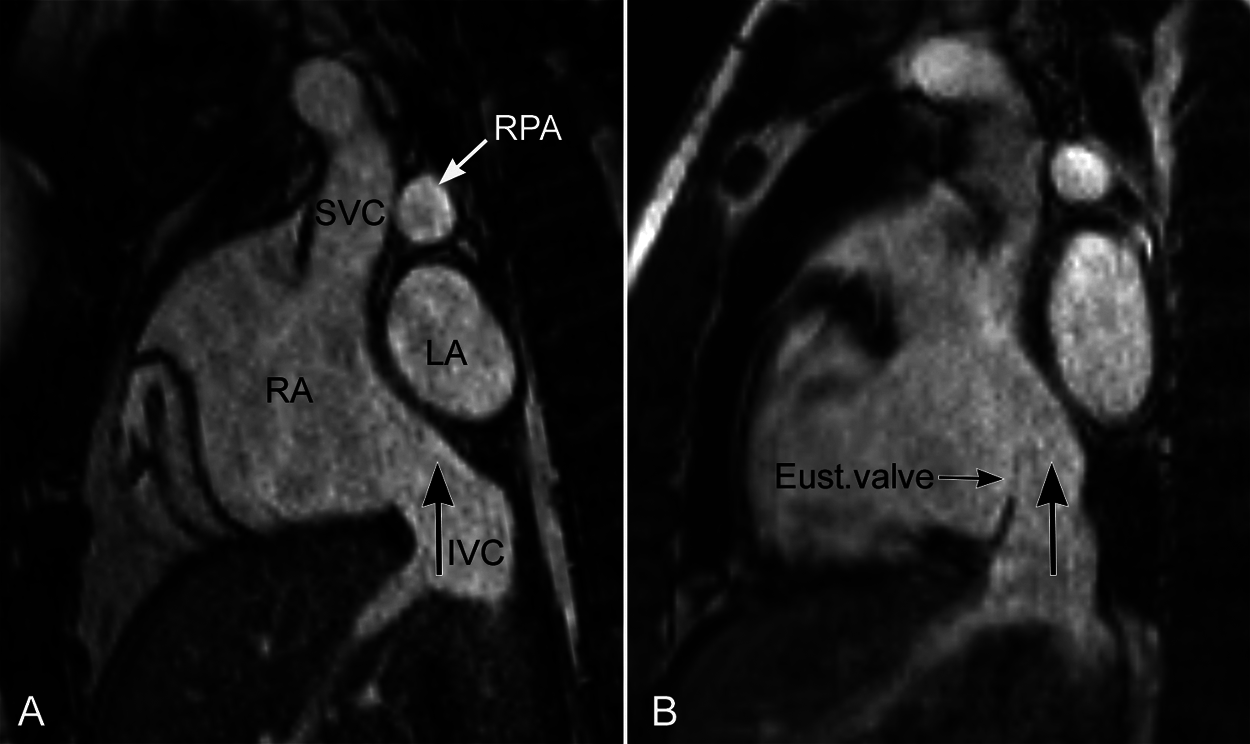

The interatrial party wall is mostly flat except for the right lateral posterior aspect where the superior and inferior venae cavae form a confluence called the sinus venarum (Fig. 3). The upper part of the sinus venarum is bounded posteriorly by the far-right side of the left atrium to which the right pulmonary veins connect. As the inferior vena cava is more posteriorly located than the superior vena cava, the party wall between the sinus venarum part of the right atrium and the adjacent left atrium–right pulmonary venous confluence is obliquely oriented with a gentle convex curvature forward and downward. Such oblique orientation of the interatrial party wall along the sinus venarum can be best appreciated in the parasagittal intercaval or bicaval imaging plane (Figs. 3A and 6). In this particular plane, the long axis of the inferior vena cava is oriented vertically toward the left atrium across the most inferior part of the interatrial party wall. The orifice of the inferior vena cava is often guarded anteriorly by a prominent membranous flap called the Eustachian valve (Fig. 6B). When present, the Eustachian valve inserts to the anterior inferior aspect of the limbus, while its superior free edge is aligned with the superior part of the limbus that in fetal medicine is named as the crista dividens [11–12,17]. The Eustachian valve is oriented in such a way to allow the inferior vena caval flow streaming into the left atrium through the patent foramen ovale during fetal life [11,17].

Figure 6: Magnetic resonance images in a parasagittal intercaval or bicaval plane from two individuals. The party wall between the right atrium (RA) and left atrium (LA) is convex forward and downward in this plane with the inferior vena caval axis (IVC, large vertical arrow) directed upward toward the left atrium above. The Eustachian valve (Eust.valve) is prominent in B. Note that the Eustachian valve is aligned with the superior part of the interatrial party wall, i.e., the limbus. RPA, right pulmonary artery; SVC, superior vena cava